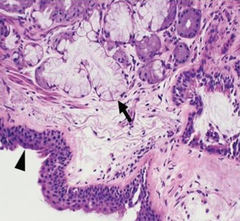

Ballooning Degeneration, Papular Stomatitis Arrows= inclusion bodies

Front

describe this oral mucosa. What is the arrow? disease?

Back